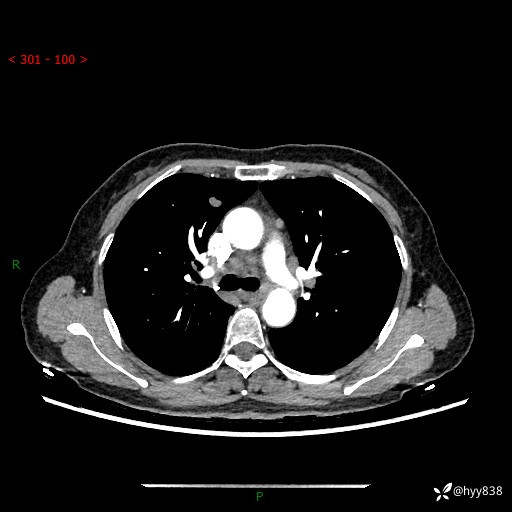

【患者信息】:58岁/女

【主诉】:体检发现肺结节

【检查】:胸部CT平扫+增强

结节病 (44)

小细胞癌 (19)